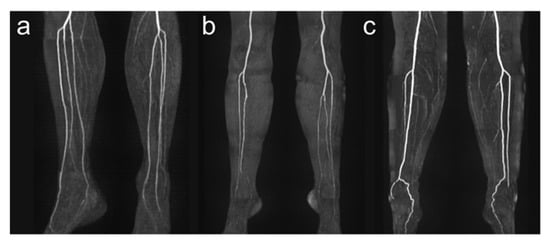

Detailed anatomic analysis of QISS-MRA source data of 100 legs according to the branching classification described by Kim et al. [19] revealed that in 87 cases (87.0%) a regular three-vessel supply was present (84.0% (42/50) in right legs and 90.0% (45/50) in left legs), in 5 cases (5.0%), a two-vessel supply (4.0% (2/50) in right legs, 6.0% (3/50) in left legs), and in no cases, a one-vessel supply. In eight legs, an irregular three-vessel supply was observed that was classified as type IC (two legs) or IIB (six legs). Four of five two-vessel supplies had a hypoplastic PT, and one leg a hypoplastic AT. Types I-B, II-A, II-C, and III-C were not identified in our patient population. Examples of anatomical vessel variations are demonstrated in Figure 3.

Figure 3.

Exemplary illustration of anatomical vessel variations of lower leg arteries. Panel (a) shows a type I-C according to Kim et al. [19] with the first exit of the PT below the knee joint with the subsequent exit of FA and AT via a common trunk. Panel (b) shows a hypoplastic PT (Type III-A) on the right side, and panel (c) shows a hypoplastic PT on both sides. Note the supply to the foot in these cases from the FA.